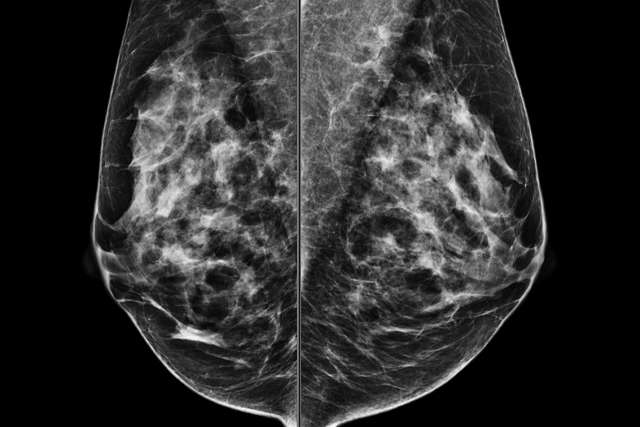

Screening Mammogram (Screening vs. Diagnostic Mammogram)

How to obtain quality breast imaging from positioning to post-processing interpretation.